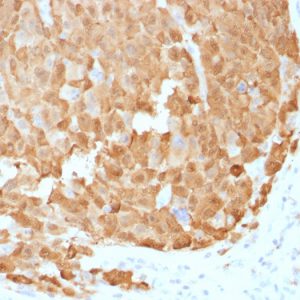

NeoBiotechnologies offers a variety of antibodies against S100A1 that have been validated for immunofluorescence and immunohistochemistry, as well as a HuProt validated option. Additionally, we hold exclusive rights to S100A1 antibodies available for licensing or collaboration https://www.neobiotechnologies.com/shop/?s=S100A1].